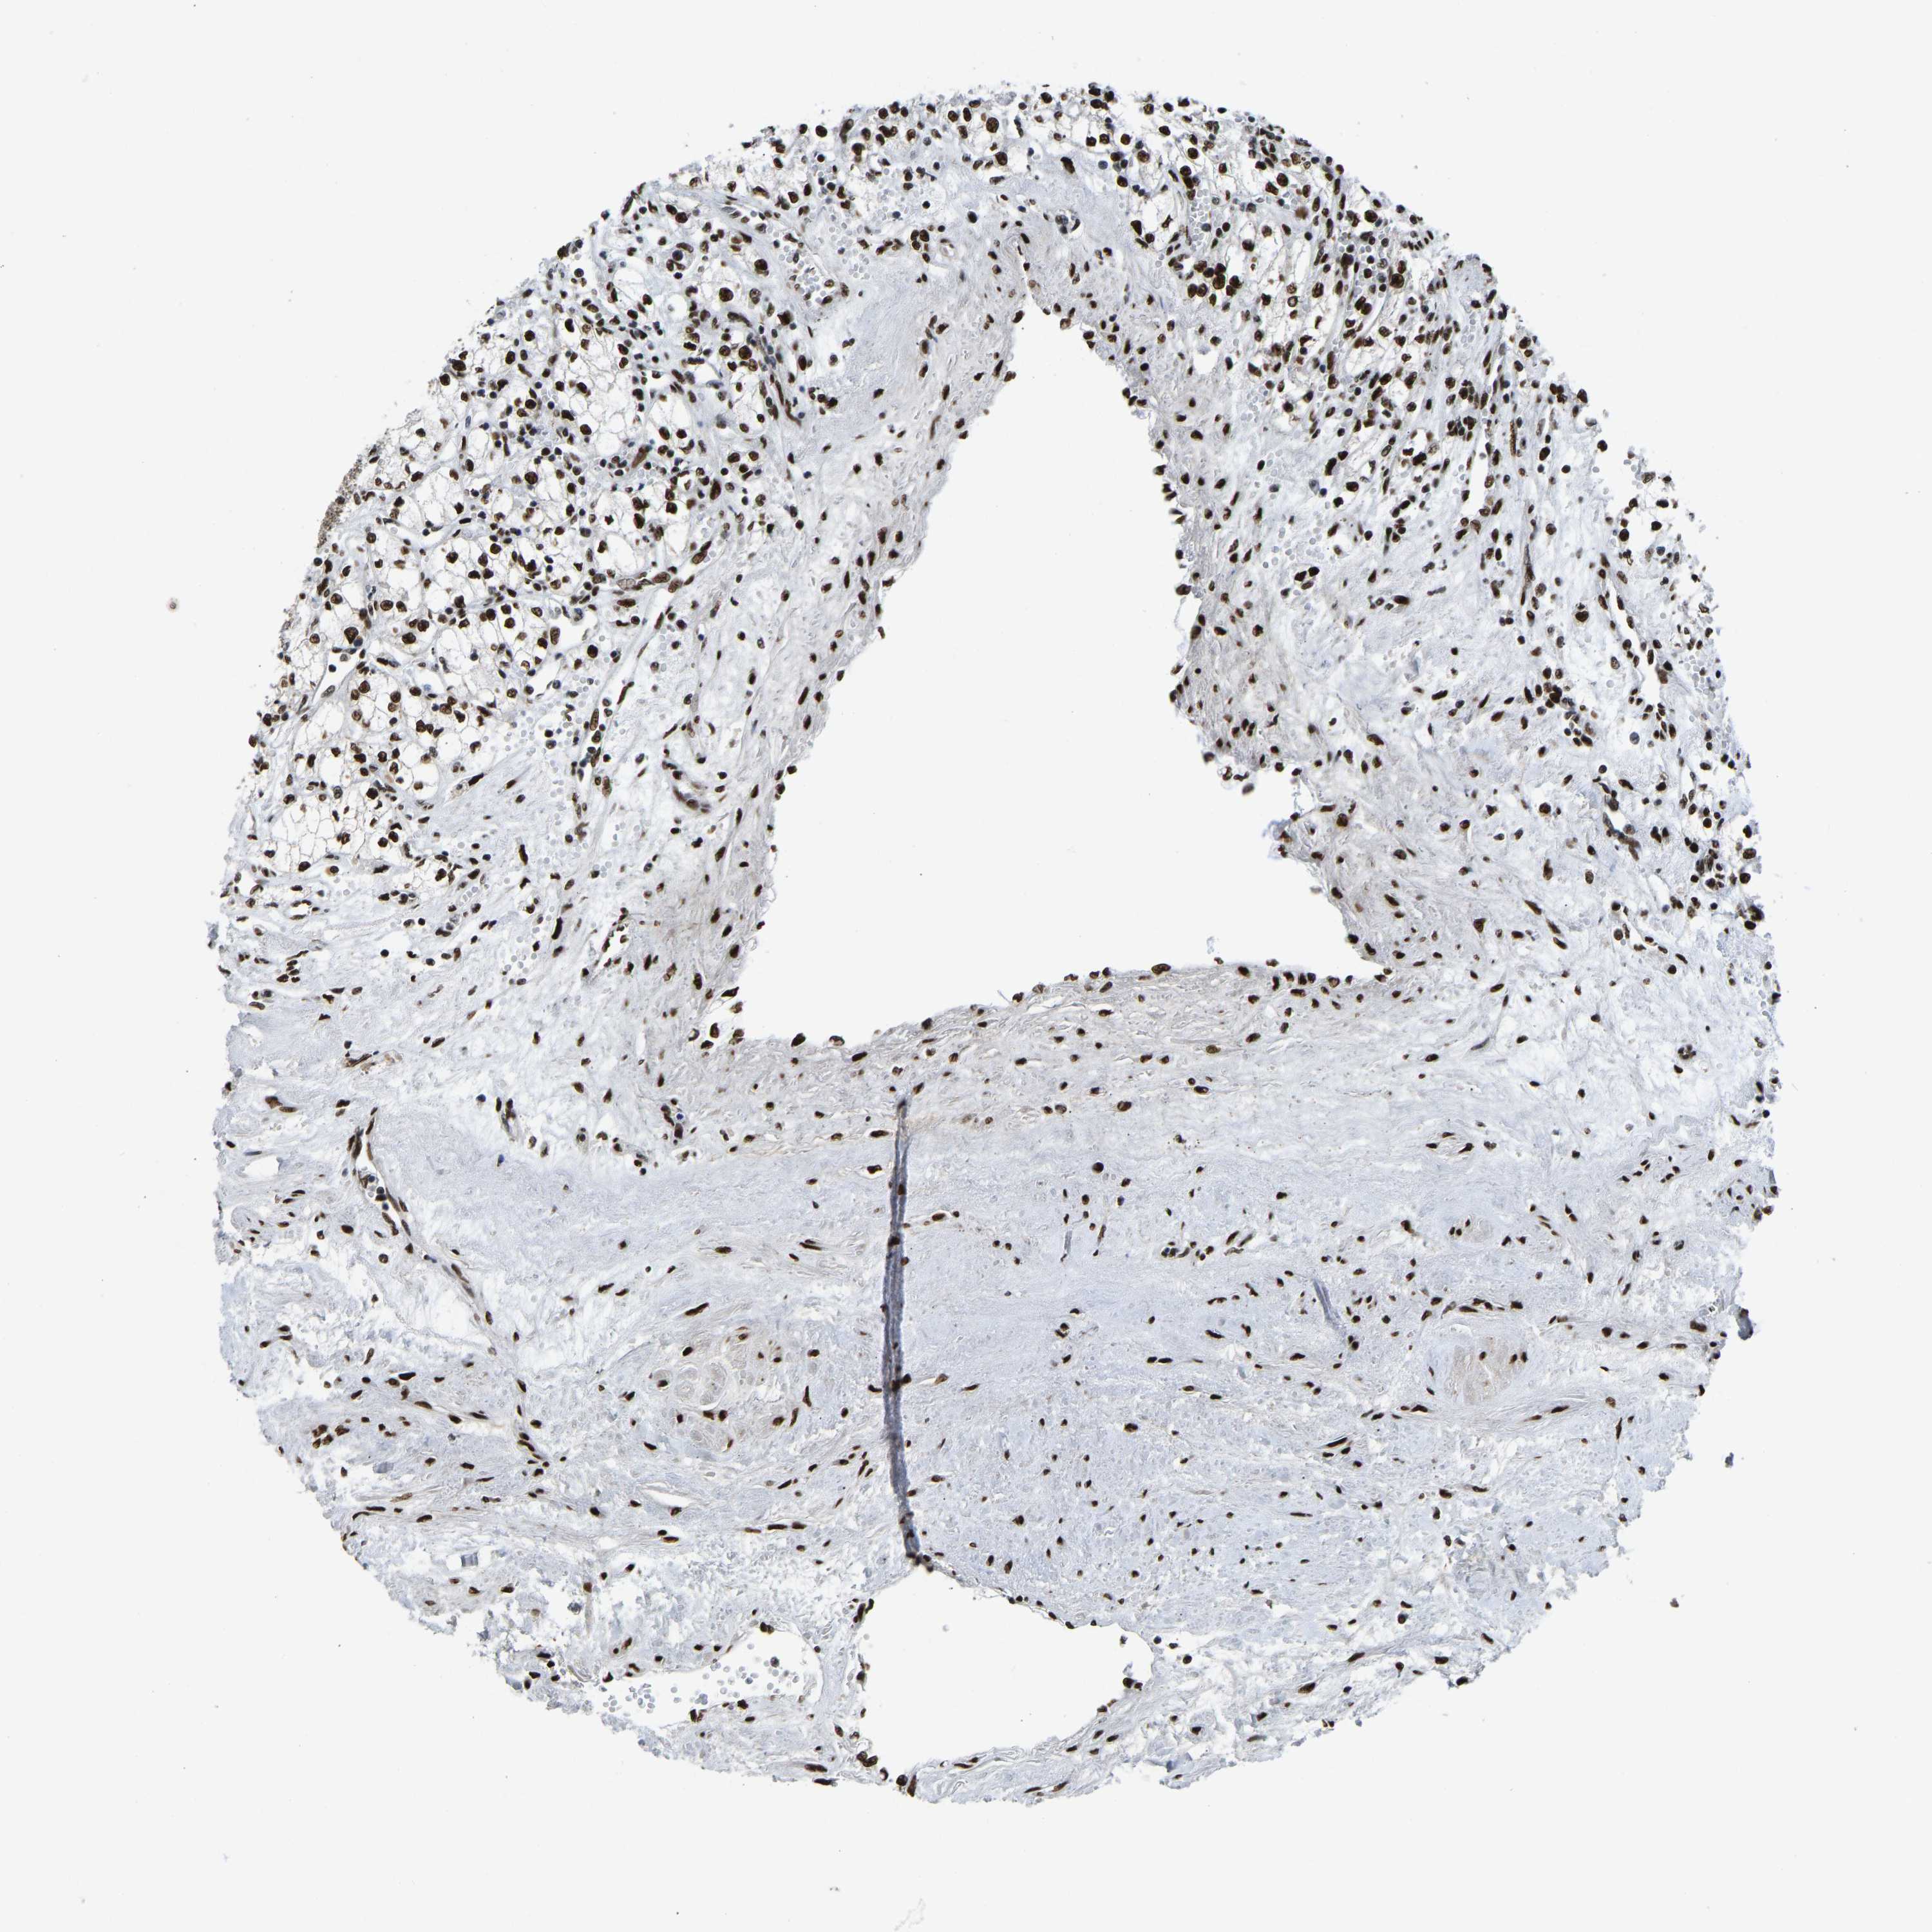

KIDNEY RENAL PAPILLARY CELL CARCINOMA (TCGA) - Interactive survival scatter ploti

The Survival Scatter plot shows the clinical status (i.e. dead or alive) for all individuals in the patient cohort, based on the same data that underlies the corresponding Kaplan-Meier plots. Patients that are alive at last time for follow-up are shown in blue and patients who have died during the study are shown in red.

The x-axis shows the expression levels (FPKM) of the investigated gene in the tumor tissue at the time of diagnosis. The y-axis shows the follow-up time after diagnosis (years). Both axes are complimented with kernel density curves demonstrating the data density over the axes. The top density plot shows the expression levels (FPKM) distribution among dead (red) and alive patients (blue). The right density plot shows the data density of the survived years of dead patients with high and low expression levels respectively, stratified using the cutoff indicated by the vertical dashed line through the Survival Scatter plot. This cutoff is automatically defined based on the FPKM cutoff that minimizes the p-score. The cutoff can be changed by dragging the vertical line or by entering a cutoff value in the square labeled "Current cut-off".

Under the Survival Scatter plot the p-score landscape (black curve; left axis) is shown together with dead median separation (red curve; right axis). Dead median separation is the difference in median mRNA expression between patients who have died with high and low expression, respectively. It is calculated as follows: median FPKM expression of dead patients with high expression - median FPKM expression of dead patients with low expression. This is intended to aid the user in visually exploring custom cutoffs and the associated p-scores and dead median separation.

Individual patient data is displayed and can be filtered by clicking on one or more of the category buttons on the top of the page. Categories describing expression level and patient information include: high, low, alive, dead, female, male and tumor stages. The scale of the x-axis can be toggled between linear and log-scale by clicking on the "x log" button. Mouse-over function shows TCGA ID, patient information and mRNA expression (FPKM) for each patient.

& Survival analysisi

Kaplan-Meier plots summarize results from analysis of correlation between mRNA expression level and patient survival. Patients were divided based on level of expression into one of the two groups "low" (under cut off) or "high" (over cut off). X-axis shows time for survival (years) and y-axis shows the probability of survival, where 1.0 corresponds to 100 percent.

FOXK1 is not prognostic in Kidney Renal Papillary Cell Carcinoma (TCGA)

Best expression cut offi

Based on the FPKM value of each gene, patients were classified into two groups and association between prognosis (survival) and gene expression (FPKM) was examined. The best expression cut-off refers the FPKM value that yields maximal difference with regard to survival between the two groups at the lowest log-rank P-value. Best expression cut-off was selected based on survival analysis .